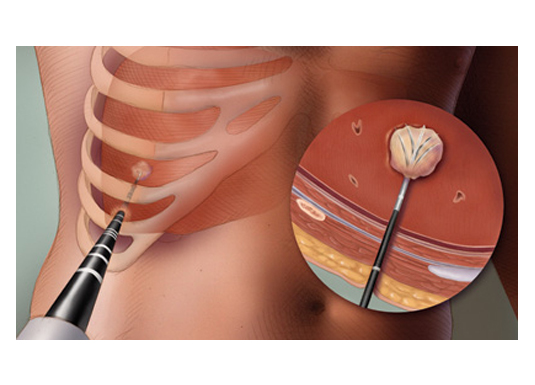

A swelling could develop anywhere in our body. It would be detected clinically by the doctor or by various imaging modalities like USG, CT or MRI. The swellings are commonly due to either infection or tumor (there are many other causes as well). The probable cause for the swelling may be guessed by imaging. However tissue sampling is must for confirmation, before starting the treatment. The swelling can be removed surgically and sent for examination to a pathologist and/or microbiologist. This however will require hospitalization, anaesthesia and also result in an ugly scar. The minimally invasive techniques for getting samples from these swellings are FNAC and Biopsy. These are predominantly done under local anaethesia and as outpatient procedures. Doing these procedures with image guidance (USG or CT) has two main advantages: one, tissue sample is taken from the swelling and not from the adjacent structures; two, we can avoid injuring the vital structures around the swelling. Thes

Requirements for FNAC of deep swellings and for biopsy: